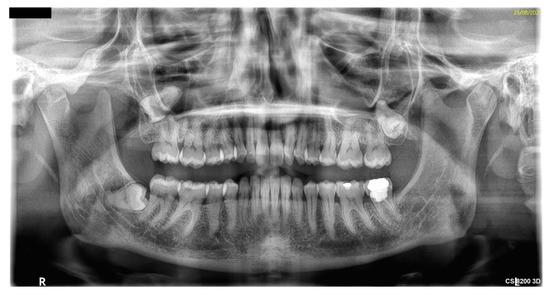

2. Case Report